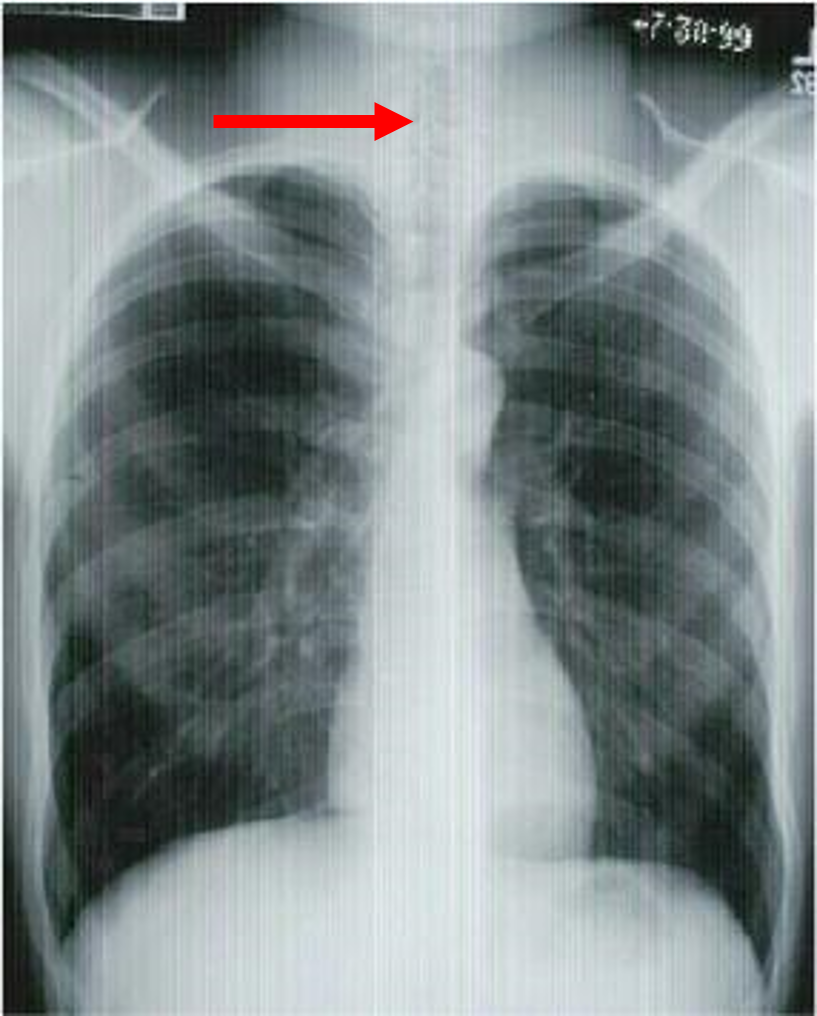

what view is this?

give three indicators

PA chest

aortic arch

diaphragm

left ventricle

liver

pulmonary artery

right atrium

right mainstem bronchus

stomach

trachea